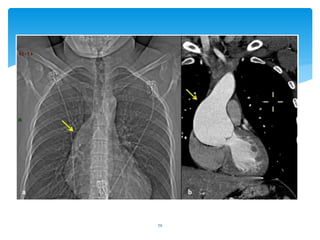

70

71